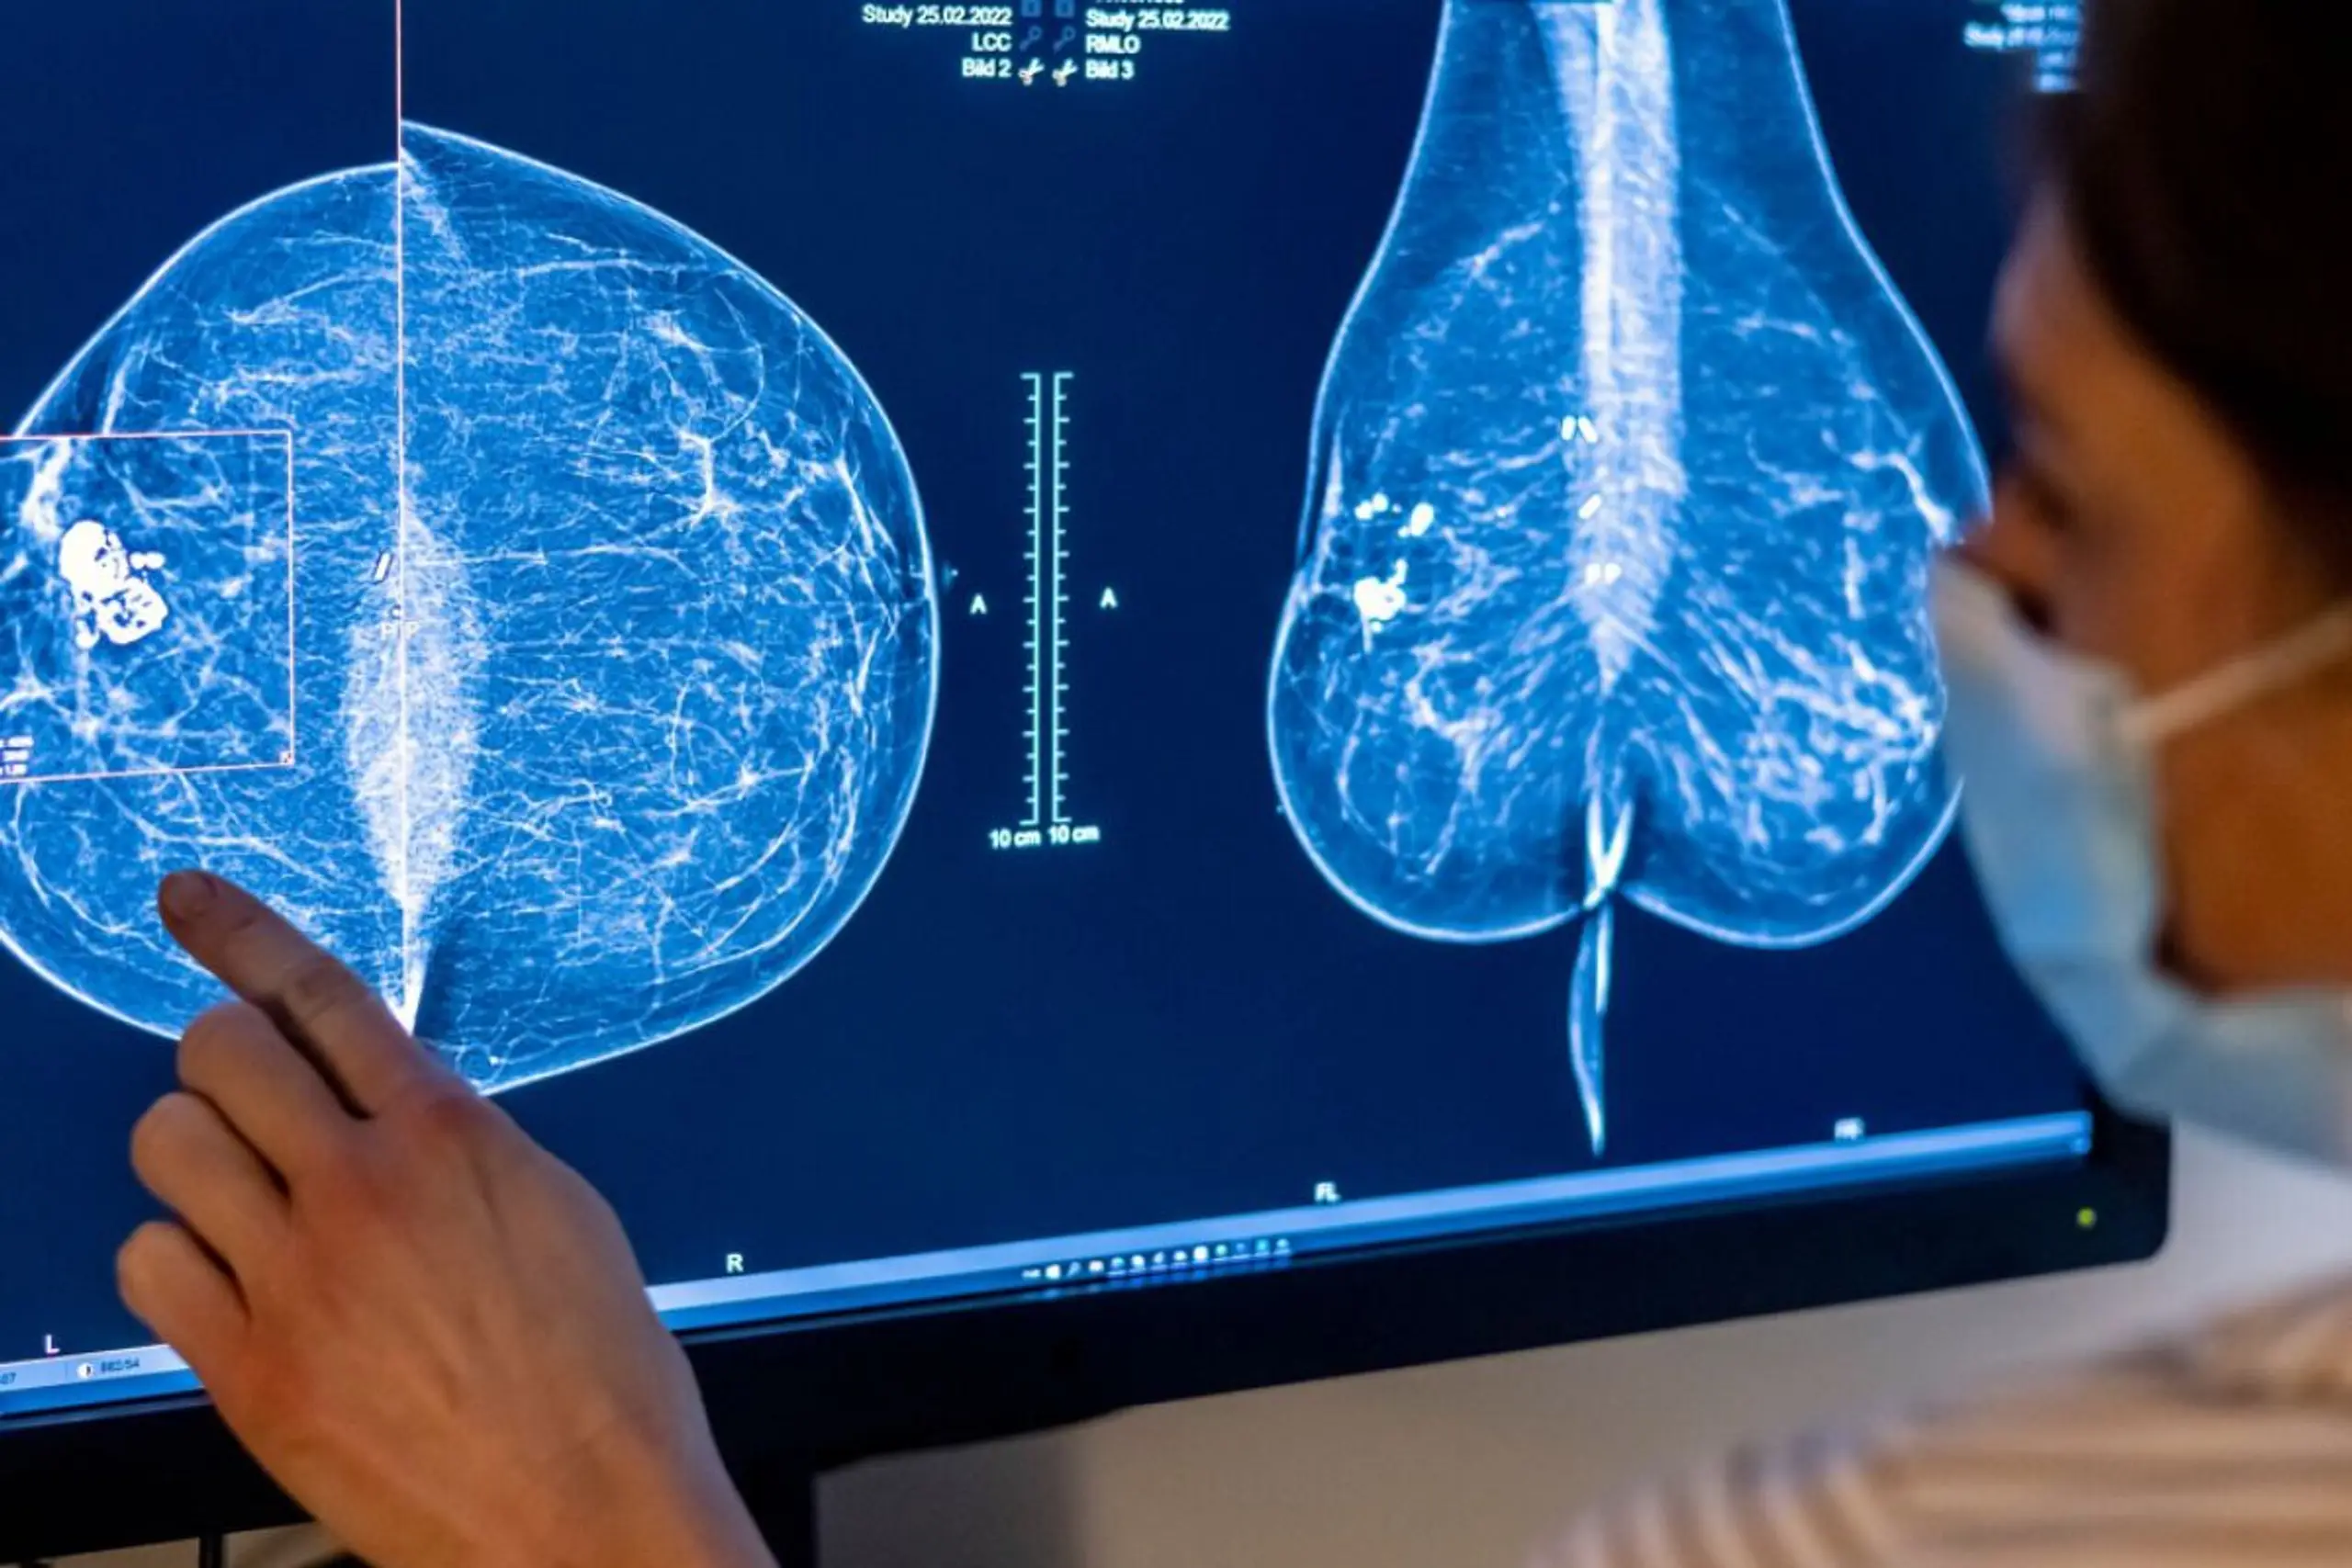

ARCHIV - 25.02.2022, Berlin: Medizinisches Personal untersucht mit einer Mammografie die Brust einer Frau auf Brustkrebs. Die Untersuchung soll bei der frühen Erkennung von Brustkrebs helfen...Für Frauen gibt es eine spezielle Untersuchung, um Krebs früh zu entdecken: die Mammografie. (zu dpa: «Globale Studie: Vier von zehn Krebstodesfällen vermeidbar») Foto: Hannibal Hanschke/dpa +++ dpa-Bildfunk +++